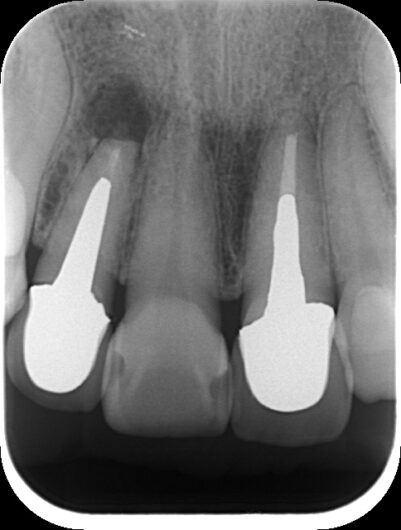

初診時レントゲン、CT

膿がおおきい